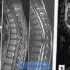

MRI

Apart from routine axial and sagittal T1 and T2 imaging additional sequences should be considered depending on the clinical concern. T2 sequences (e.g. gradient echo, SWI) are more sensitive to hemorrhage, while STIR sequences are more sensitive to associated ligamentous injury.

- Spinal cord swelling

- focal cord enlargement at the level of trauma without signal change 5 best seen on sagittal T1

- Spinal cord edema

- as per swelling but with additional increased T2 signal

- Spinal cord contusion

- thick high T2 signal rim around small central low T1 signal above or below the level of trauma.

- blooming on T2 sequences

- Intramedullary hemorrhage

- thin high T2 signal rim around large central low T1 signal 5

- blooming on T2* sequences

- see aging blood on MRI for other timescales

- Spinal cord transection

- discontinuity of cord best seen on sagittal sequences